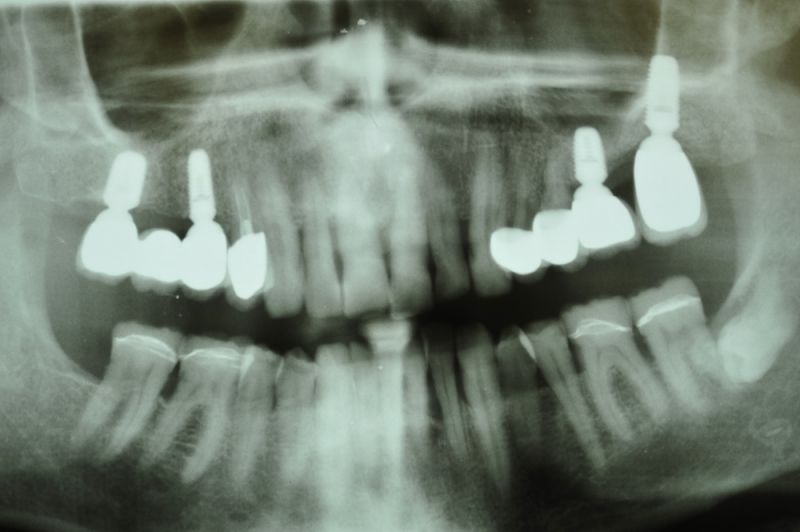

Rekonstruierter CMD Patient erscheint zum vierteljährlichen Recall

Wie üblich erscheint der Patient zum Recall.

Alles siehgt perfgekt aus. 2 mm tiefe Taschen, perfekte Mundhygiene. Die Arbeit funktioniert!